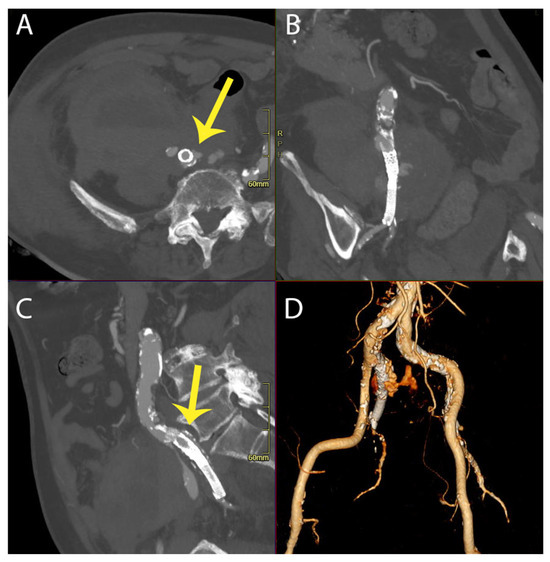

This intervention successfully managed the recurrent rupture, and the patient achieved clinical stability, leading to their discharge on the 35th postoperative day. Se Figure 3.

Figure 3. Multiplanar reformation (MPR view in axial (A), coronal (B), sagittal (C)) and 3D reconstruction (D) of postoperative CT angiography demonstrating that the endograft (Endurant II limb) extends to cover the common and external iliac arteries, along with embolization of the right internal iliac artery.